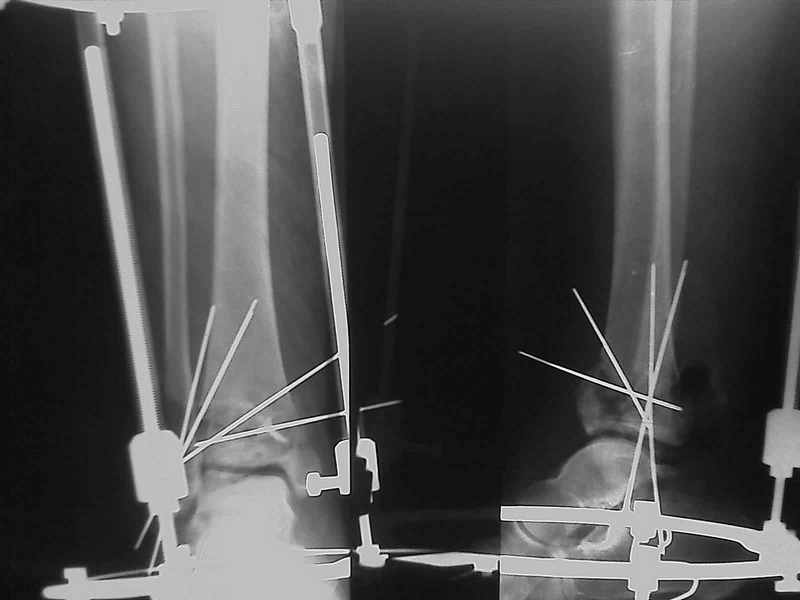

Яков изложил все необходимые аспекты лечения переломов пилона, и, не желая менять тему, решил выставить нашу точку зрения в двух клинических примерах.

Дополнительные ренгенограммы после дистракции и

обязательная комьютерная томография дают возможности разузнать топографию расположения фрагментов, что немаловажно для планирования хирургического доступа.

По апексу фрагмента ориентируется при планировании

фиксации, также предоперационно определяется

направление фиксирующего материала: шурупа или спицы с упорной площадкой.

Первичная пластина или интрамедуллярный фиксатор на малоберцовую зависит от характера перелома, косые и многооскольчатые пластинами, а поперечных можно интрамедуллярными фиксаторами. Восстановленная длина малоберцовой служит ориентиром и помогает определению высоты большеберцовой во время восстановления.

Переломы пилона сопровождаются ударом со сминанием в метафизарной части большеберцовой, то есть со значительной потерей костного объема.

При репозиции суставных поверхностей образуются полости в метафизарных отделах, без заполнения их

структуральными элементами невозможно предохраниться от посттравматической деформации. Латеральная колонна удерживается малоберцовой поэтому голень деформируется в варус.

Здесь выставлена пара случаев перелома пилона, оба

случая леченные этапным наружным фиксатором.

Второй случай фиксирован аппаратом Илизарова.